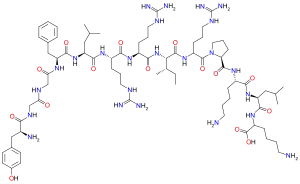

Opioid peptides

Dynorphins

Structures

| Dynorphins | ||||

|---|---|---|---|---|

Big dynorphin Big dynorphin |

Dynorphin A Dynorphin A |

Dynorphin B Dynorphin B | ||

Endomorphins

Endorphins

Structures

Enkephalins

Structures

| Enkephalins | ||||

|---|---|---|---|---|

DAMGO DAMGO |

||||

Propeptides

Others / unknown

- Adrenorphin

- Amidorphin

- Biphalin

- Casokefamide

- Casomorphins

- Cytochrophin-4

- DALDA (Tyr-D-Arg-Phe-Lys-NH2)

- Deltorphin I

- Deltorphin II

- Deprolorphin

- Dermorphin

- DPDPE

- Frakefamide

- Gliadorphin

- Gluten exorphins

- Hemorphin-4

- Metkefamide

- Morphiceptin

- Nociceptin

- Octreotide

- Opiorphin

- Rubiscolin

- Soymorphins

- Spinorphin

- TRIMU 5

- Tynorphin

- Valorphin

- Zyklophin

Structures

| Other or unknown opioid peptides | ||||

|---|---|---|---|---|

Adrenorphin Adrenorphin |

Amidorphin Amidorphin |

Casomorphin Casomorphin |

DALDA DALDA |

|

DPDPE DPDPE |

Endomorphin-1 Endomorphin-1 Endomorphin-2 Endomorphin-2 |

Gliadorphin Gliadorphin |

Morphiceptin Morphiceptin | |

Nociceptin Nociceptin |

Octreotide Octreotide |

Opiorphin Opiorphin |

Rubiscolin Rubiscolin |

TRIMU 5 TRIMU 5 |